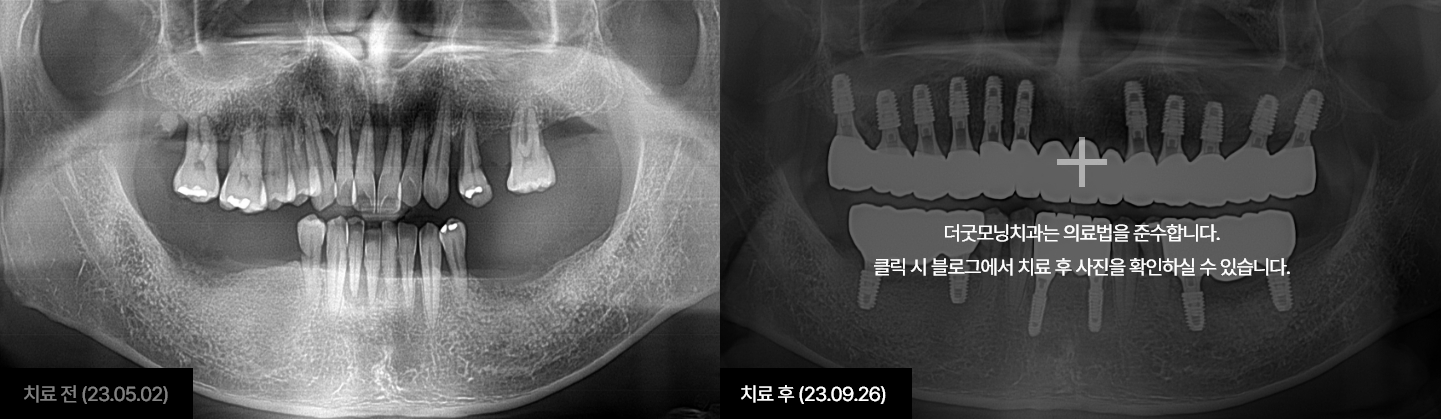

임플란트는 시술하는 의사의 수술 경험, 노하우에 따라 진료 결과가 달라지는

시술입니다.

잇몸뼈에 식립하여 자연치아를 대체해 주는 보철치료인 만큼

잇몸과

잇몸뼈에 대해 전문성이 높은 치주과 전문의가 진료해야 합니다.

더굿모닝치과는

보건복지부 인증 치주과+통합치의학과 더블보드 전문의가 직접 진료하며,

진단부터 식립, 최종 보철물까지 꼼꼼하게 완성해 드릴 것을

약속드립니다.

더굿모닝치과 블로그에서 해당 사례를 자세히 확인하실 수 있습니다.